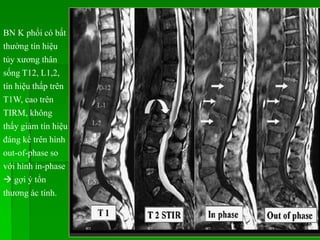

BN K phổicó bất thường tín hiệu tủy xương thân sống T12, L1,2, tín hiệu thấp trên T1W, cao trên TIRM, không thấy giảm tín hiệu đáng kể trên hình out-of-phase so với hình in-phase  gợi ý tổn thương ác tính.

Hydrosyringomyelia  Là vùngdịch trong tủy sống, thông hay không thông với ống trung tâm. Có 2 dạng: • Thông thương (15-20%) với não thất IV: điển hình kèm não úng thủy, xảy ra với xuất huyết khoang dưới nhện, viêm màng não do TB di căn (leptomeningeal carcinomatosis). • Không thông thương (80%) với não thất IV: do Chiari I, Chiari II, chấn thương tủy sống, u nội tủy, tổn thương chèn ép ngoài tủy.  MRI: tủy lớn với khoang dịch ở trung tâm hay cạnh trung tâm tủy, tín hiệu dịch tương đương dịch não tủy. Tăng tín hiệu tủy trên T2W quanh vùng rỗng tủy do phù, tăng sinh mô đệm hay nhuyễn tủy. Rỗng tủy lành tính không bắt thuốc tương phản sau tiêm. Chiari I có thể kèm tích dịch ống nội tủy dạng chuỗi hạt.